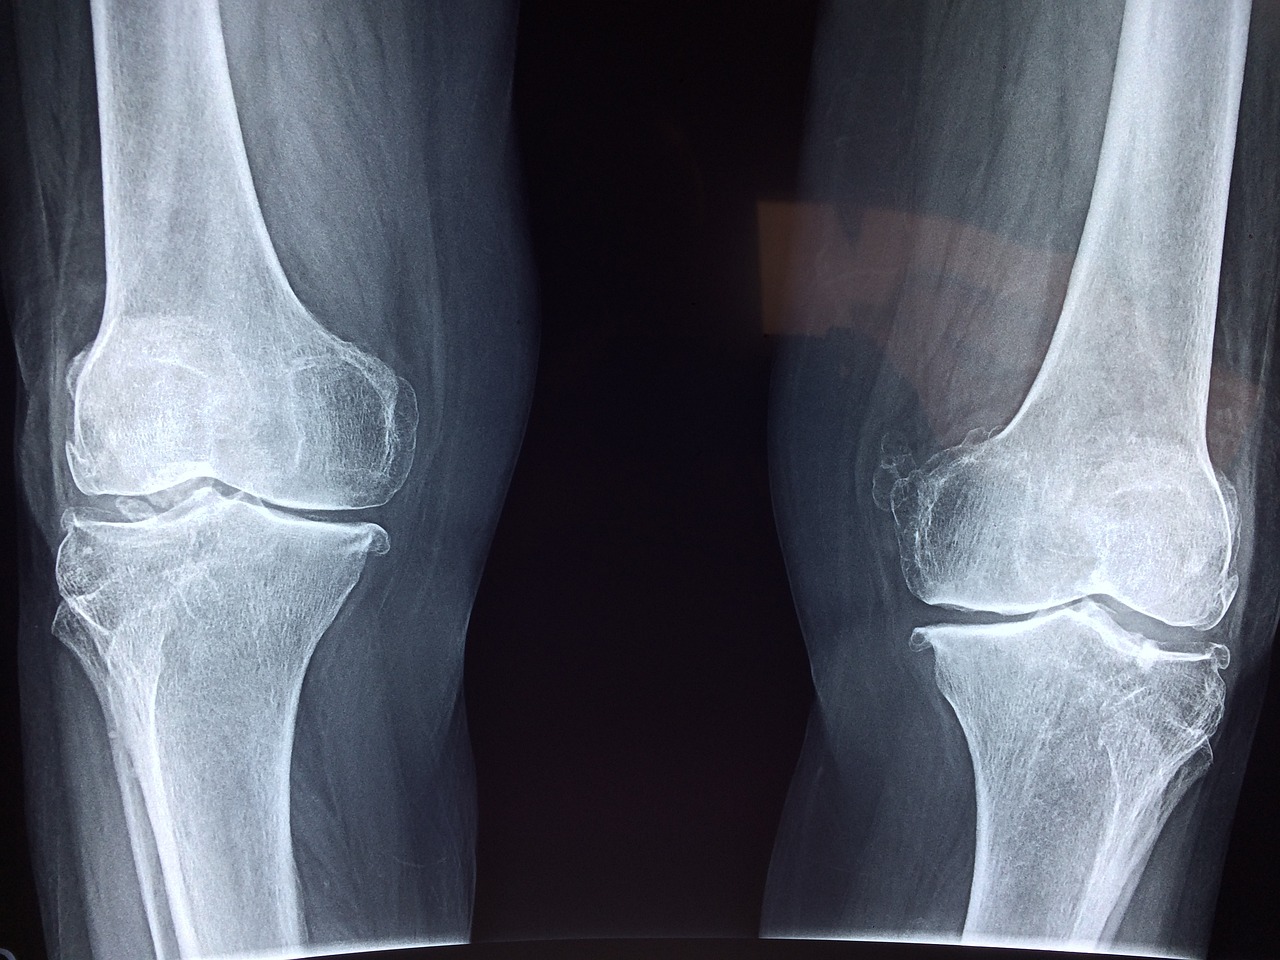

Digitales Röntgen

Unsere Praxis ist mit einem digitalen Röntgengerät ausgestattet, bei dem digitale Technologien zur Erfassung und Verarbeitung von Röntgenbildern verwendet werden. Das bildgebende Verfahren wird insbesondere zur Beurteilung von Gelenk- und Knochenverletzungen sowie -veränderungen eingesetzt.